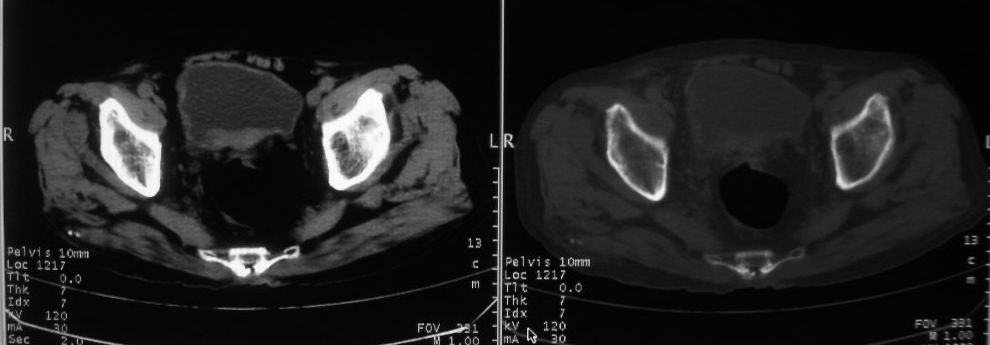

以下是引用zjzjr在2008-10-3 12:59:00的发言:[br]前列腺癌伴左髂骨\\腰椎转移可能性大.

以下是引用卜一在2008-10-3 13:40:00的发言:[br]前列腺癌!左髂骨\\腰椎转移?建议行全身骨扫描!

以下是引用深泽交通医院在2008-10-3 15:33:00的发言:[br]前列腺实性增大伴分叶状,与包膜间隙境界不清;椎体松质区间结节样密度影,考虑:前列腺癌,并椎体成骨性转移